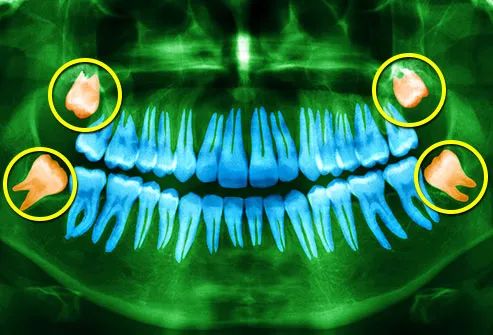

缺少压力

如今,牙齿畸形也是十分常见的疾病。每十个人中有九个人的牙齿至少会有稍微错位或咬合不正,并且有四分之三的人,他们的智齿没有足够的空间来适当地露出来。简单地说,我们的牙齿不适合我们的下巴。就像龋齿一样,造成这一现象的原因是我们的祖先的牙齿从未遇到过的口腔环境的不平衡。

他发现,生活在传统生活方式中的澳大利亚原住民比欧洲移民的牙科患者更容易掉牙。原住民还拥有完美的牙弓——他们的前牙是笔直的,而他们的智齿已经完全暴露并正常运转。贝格推断,自然界希望相邻牙齿之间的磨损能够减少口腔中的空间需求。他认为,考虑到这一点,颌骨长度是通过进化“预先设定好的”。

因此,我们的牙齿实际上是为原始环境中的坚硬食物进化的,而到了现代,柔软、清洁的饮食却破坏了牙齿尺寸和下颌长度之间的平衡。所以,在口腔外科,为了让我们的牙齿适应今天的口腔环境,都不得不依靠拔除牙齿。

科鲁奇尼认为,牙齿的大小已经过预先编程,可以适应在成长过程中承受机械应力水平的下巴,这与儿童期自然饮食相符。随后,当颌骨在发育过程中没有得到所需的刺激时,牙齿在前端变得拥挤而在后部受到冲击。他通过对猴子进行的实验工作证实了这一假设,即那些喂养较软饮食的猴子下颚较小且牙齿受到影响。